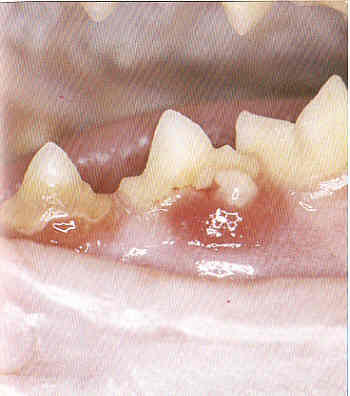

Milchzähne

Wenn Milchzähne nicht rechtzeitig ausfallen, so bildet sich mit den nachkommenden bleibenden Zähnen eine doppelte Zahnreihe. Solche Milchzähne behindern die bleibenden Zähne und müssen gezogen werden.

Zahnfleischentzündung

Eitrige und nichteitrige Zahnfleischentzündungen gefährden das Zahnbett und können zu Zahnverlust führen, Manchmal sind sie auch Folgen schwerer Infektionserkrankungen.

Zahnstein

Zahnstein ist die größte Gefahr, die dem bleibenden Gebiss droht. Nicht nur übler Mundgeruch, sondern auch Entzündungen des Zahnfleisches und Wurzelvereiterungen, Zahnfisteln, Zahnausfall und Allgemeinerkrankungen können die Folge sein.

Zahnfleischgeschwülste (Epuliden) finden sich besonders häufig beim Boxer. Sie könne die Zahnreihen völlig überwuchern.